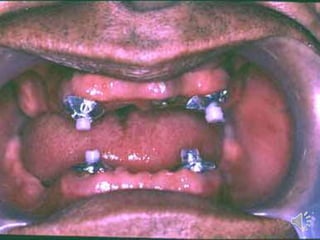

ABUTMENT WITH ATTACHMENTS

Attachments are small precision devices.

Objective is to improve retention of denture base.

Most attachments are secured to abutment by a cast coping.

Consists of two parts o Male o Female

Advantages of bar attachments :

igidly splint the teeth

rovides good retention, stability and support

rovides cross arch stabilization